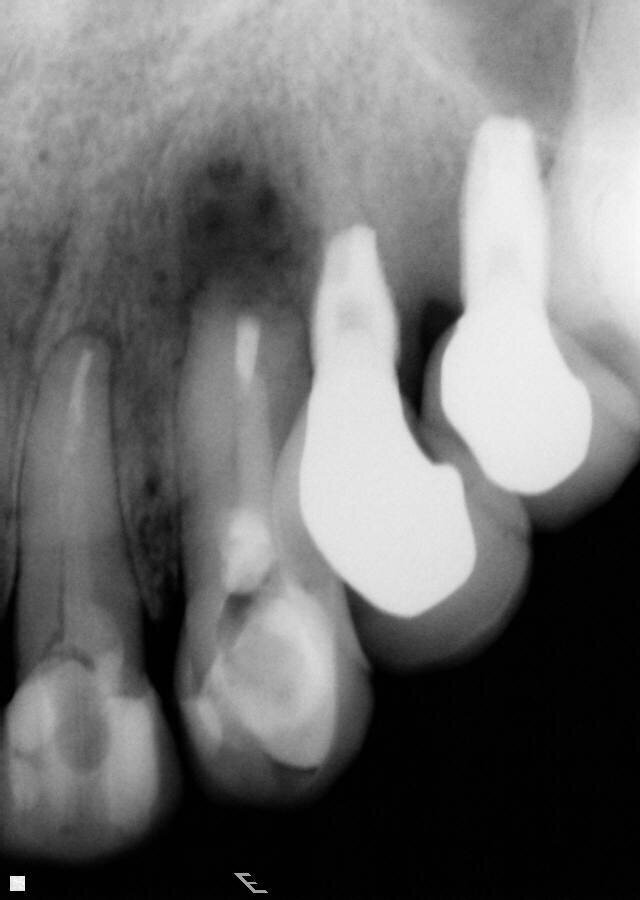

Fig. 5: Periapical radiographic follow-up after 30 and 90 days, showing a fast regression of the periapical lesion and a bone repair.

Fig. 6: Periapical radiographic follow-up after 30 and 90 days, showing a fast regression of the periapical lesion and a bone repair.

After the clot formation, interrupted sutures were performed and the patient was medicated with antibiotics and anti-inflammatories for five days. Chlorhexidine mouthwashes were also recommended. The sutures were removed after 10 days. The radiographic follow-up was performed after 30 and 90 days (Figs. 5, 6).